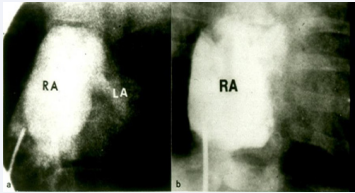

Figure 12 Selected cine frames of right atrial (RA) cineangiogram in postero-anterior projection of two patients with tricuspid atresia demonstrating blind ending of the right atria. Faint opacification of left atrium (LA) is seen a [38].

Figure 12:

Selected cine frames of right atrial (RA) cineangiogram in postero-anterior projection of two patients with tricuspid atresia demonstrating blind ending of the right atria. Faint opacification of left atrium (LA) is seen a [38].

As alluded to in the preceding section, the diagnosis of TA can be made by clinical, chest X-ray, and ECG findings and confirmed by echocardiographic studies, and therefore, cardiac catheterization and selective cineangiography are not necessary to establish the diagnosis [31,37]. There is no need for cardiac catheterization even in those neonates with severe arterial desaturation; the diagnosis of TA made on the basis of clinical and echo-Doppler studies is adequate to make management decisions. However, catheterization may be indicated: 1. If balloon atrial septostomy is necessary and 2. Prior to bidirectional Glenn and Fontan surgery in order to define the pulmonary artery pressures and anatomy. For a detailed discussion of cardiac catheterization and selective cineangiography, the interested reader is referred elsewhere [31,35,37,38]; however, some typical angiographic pictures will be presented in Figures 12 to 17.